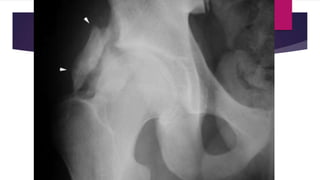

 Late stage (maturation phase)

 Mass becomes bony hard and easily discernible from its surrounding

tissue.

 Pain reduces dramatically.

 Mass may merge with bone resembling osteochondroma.

 Movements at associated joint may be limited in large mass.

 Zonation phenomenon – pattern of mineralization at periphery which is

more mature than central region that is still evolving. This differentiates

it from extraskeletal osteosarcoma.

 Late stage(maturation phase)  Mass becomes bony hard and easily discernible from its surrounding tissue.  Pain reduces dramatically.  Mass may merge with bone resembling osteochondroma.  Movements at associated joint may be limited in large mass.  Zonation phenomenon – pattern of mineralization at periphery which is more mature than central region that is still evolving. This differentiates it from extraskeletal osteosarcoma.  MRI – overall reduced due to calcification. Important differentiating feature could be presence of central signal intensity similar to marrow.